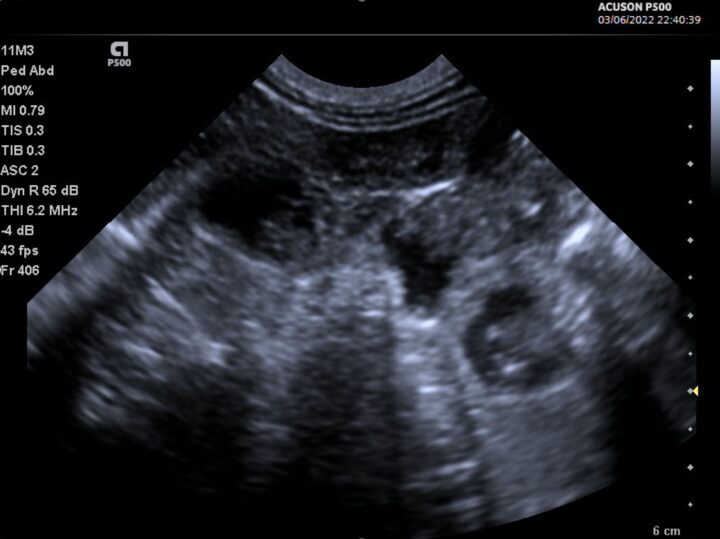

Manipulating your imaging plane is essential for certain measurements, such as crown–rump length and biparietal diameter. Still images can be ambiguous – Figure 3, for example, is not pregnancy – so watching a video clip (Video 1) instead makes this image more interpretable.

(Video 1)